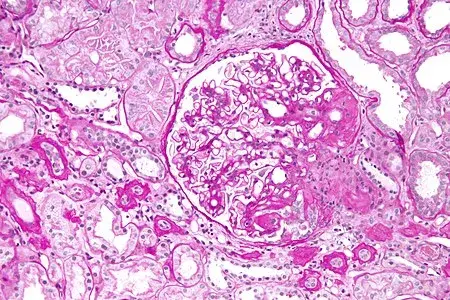

Desescalada de inmunosupresores en la Nefritis Lúpica

Desescalada de inmunosupresores en la Nefritis Lúpica

La desescalada de inmunosupresores en la Nefritis Lúpica siempre es un desafío; consulte este artículo de revisión con un algoritmo muy práctico.